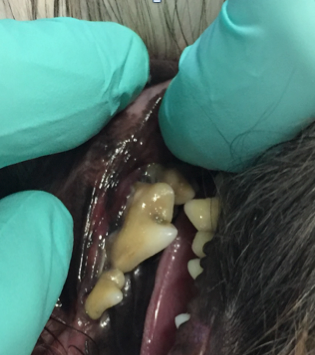

Als ich bei Leila ins Maul schaute, staunte ich schon nicht schlecht. Ich sah die Besitzerin an und fragte: „Wie alt war Leila noch mal?“ Leila war tatsächlich erst drei Jahre alt und doch wusste ich da schon, dass wir wahrscheinlich keinen Zahn retten könnten. Man sieht es wirklich nur, wenn man etwas genauer hinschaut: Leilas Zahnhälse lagen alle frei, und eitrige Beläge kamen aus der Tiefe des Zahnfachs (Abb. 2 - 5).

In Narkose sah man auf Leilas Röntgenbildern dann das gesamte Ausmaß ihrer Zahnerkrankung. Bis auf die Canini wiesen alle Zähne hochgradige Wurzelentzündungen mit Osteolysen des Kieferknochens auf. Deshalb konnte man auch schon von außen die Zahnhälse freiliegend sehen. Im Wurzelbereich waren die Veränderungen so schlimm, dass der Unterkiefer kurz vor einer Fraktur stand.

Solche Veränderungen treten oft bei einer hochgradigen Parodontitis auf. Eine Parodontitis ist die Entzündung des gesamten Zahnhalteapparates (also des Kieferknochens, des Zements, der Paradontalfasern und des Zahnfleischs) und wird durch die Bakterien, welche im Plaque enthalten sind, hervorgerufen. Diese zerstören die Anheftung der Gingiva am Zahn, und die Bakterien können bis zur Wurzel vordringen. Hier rufen sie Entzündungsreaktionen des Kieferknochens und der Gingiva hervor, wodurch beide sich zurückziehen und tiefe Paradontaltaschen entstehen lassen. Doch Leila hatte, wie auf den Bildern schön zu sehen ist, kaum Zahnstein oder Plaque.